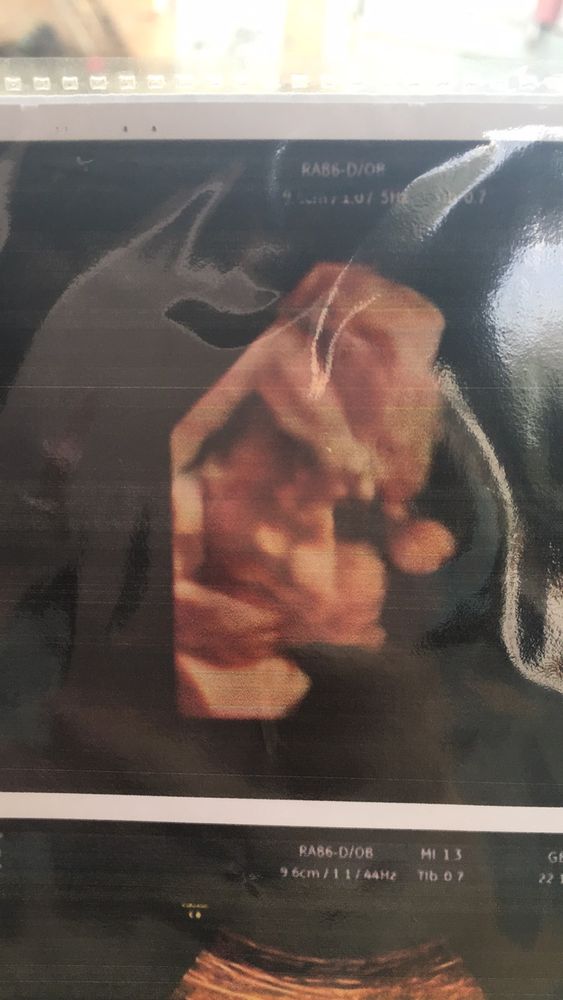

Результаты: УЗИ, КТГ, доплера, скринингаНам 29 неделек, сегодня были на узи, сказали по узи 29.4 недельки, вес 1391г.

однократное обвитие есть, но это не страшно.

малыш все время держал ручку возле лица и не дал сделать фото😭а так хотелось